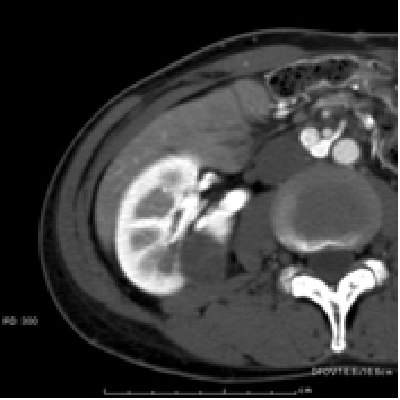

腎がんが多発するフォンヒッペルリンドウ病の患者様で、左腎はすでに他院で摘出されており、右腎しかない単腎の症例。ラジオ波治療後に腫瘍は完全に死滅している。この患者様はこの後、もう一つ別にあった腎がんも同様に治療された。このようにラジオ波治療は腎機能を低下させず、繰り返して治療できることから、このような単腎の多発腎がんでも治療が可能である。